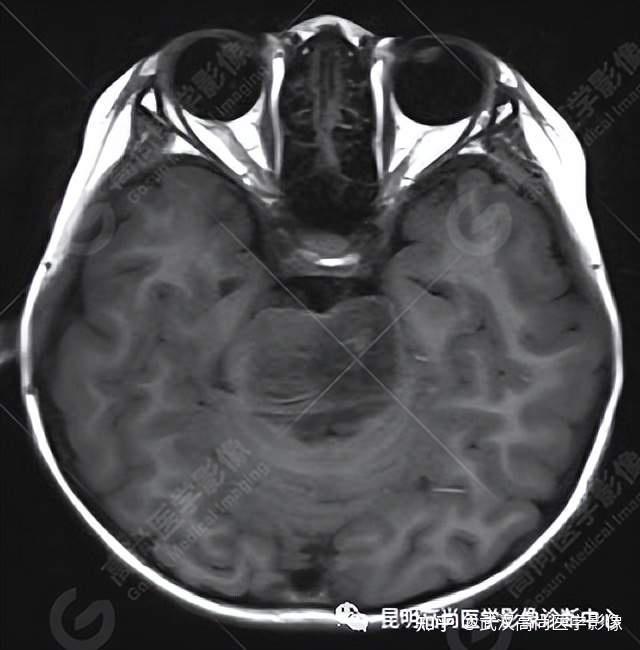

脑干弥漫性中线胶质瘤一例「武汉高尚医学影像」

图片尺寸640x650